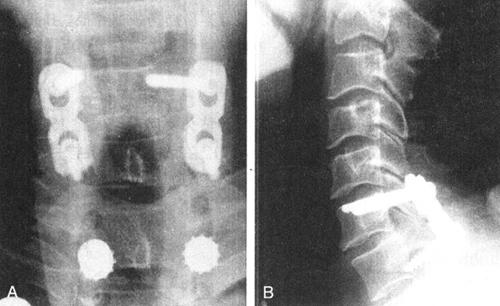

图13-23 48岁女性C1爆裂骨折,枕颈及C1~C2关节不稳。做后路枕颈固定,镶嵌植骨。枕骨用双皮质螺钉,C2为椎弓根钉